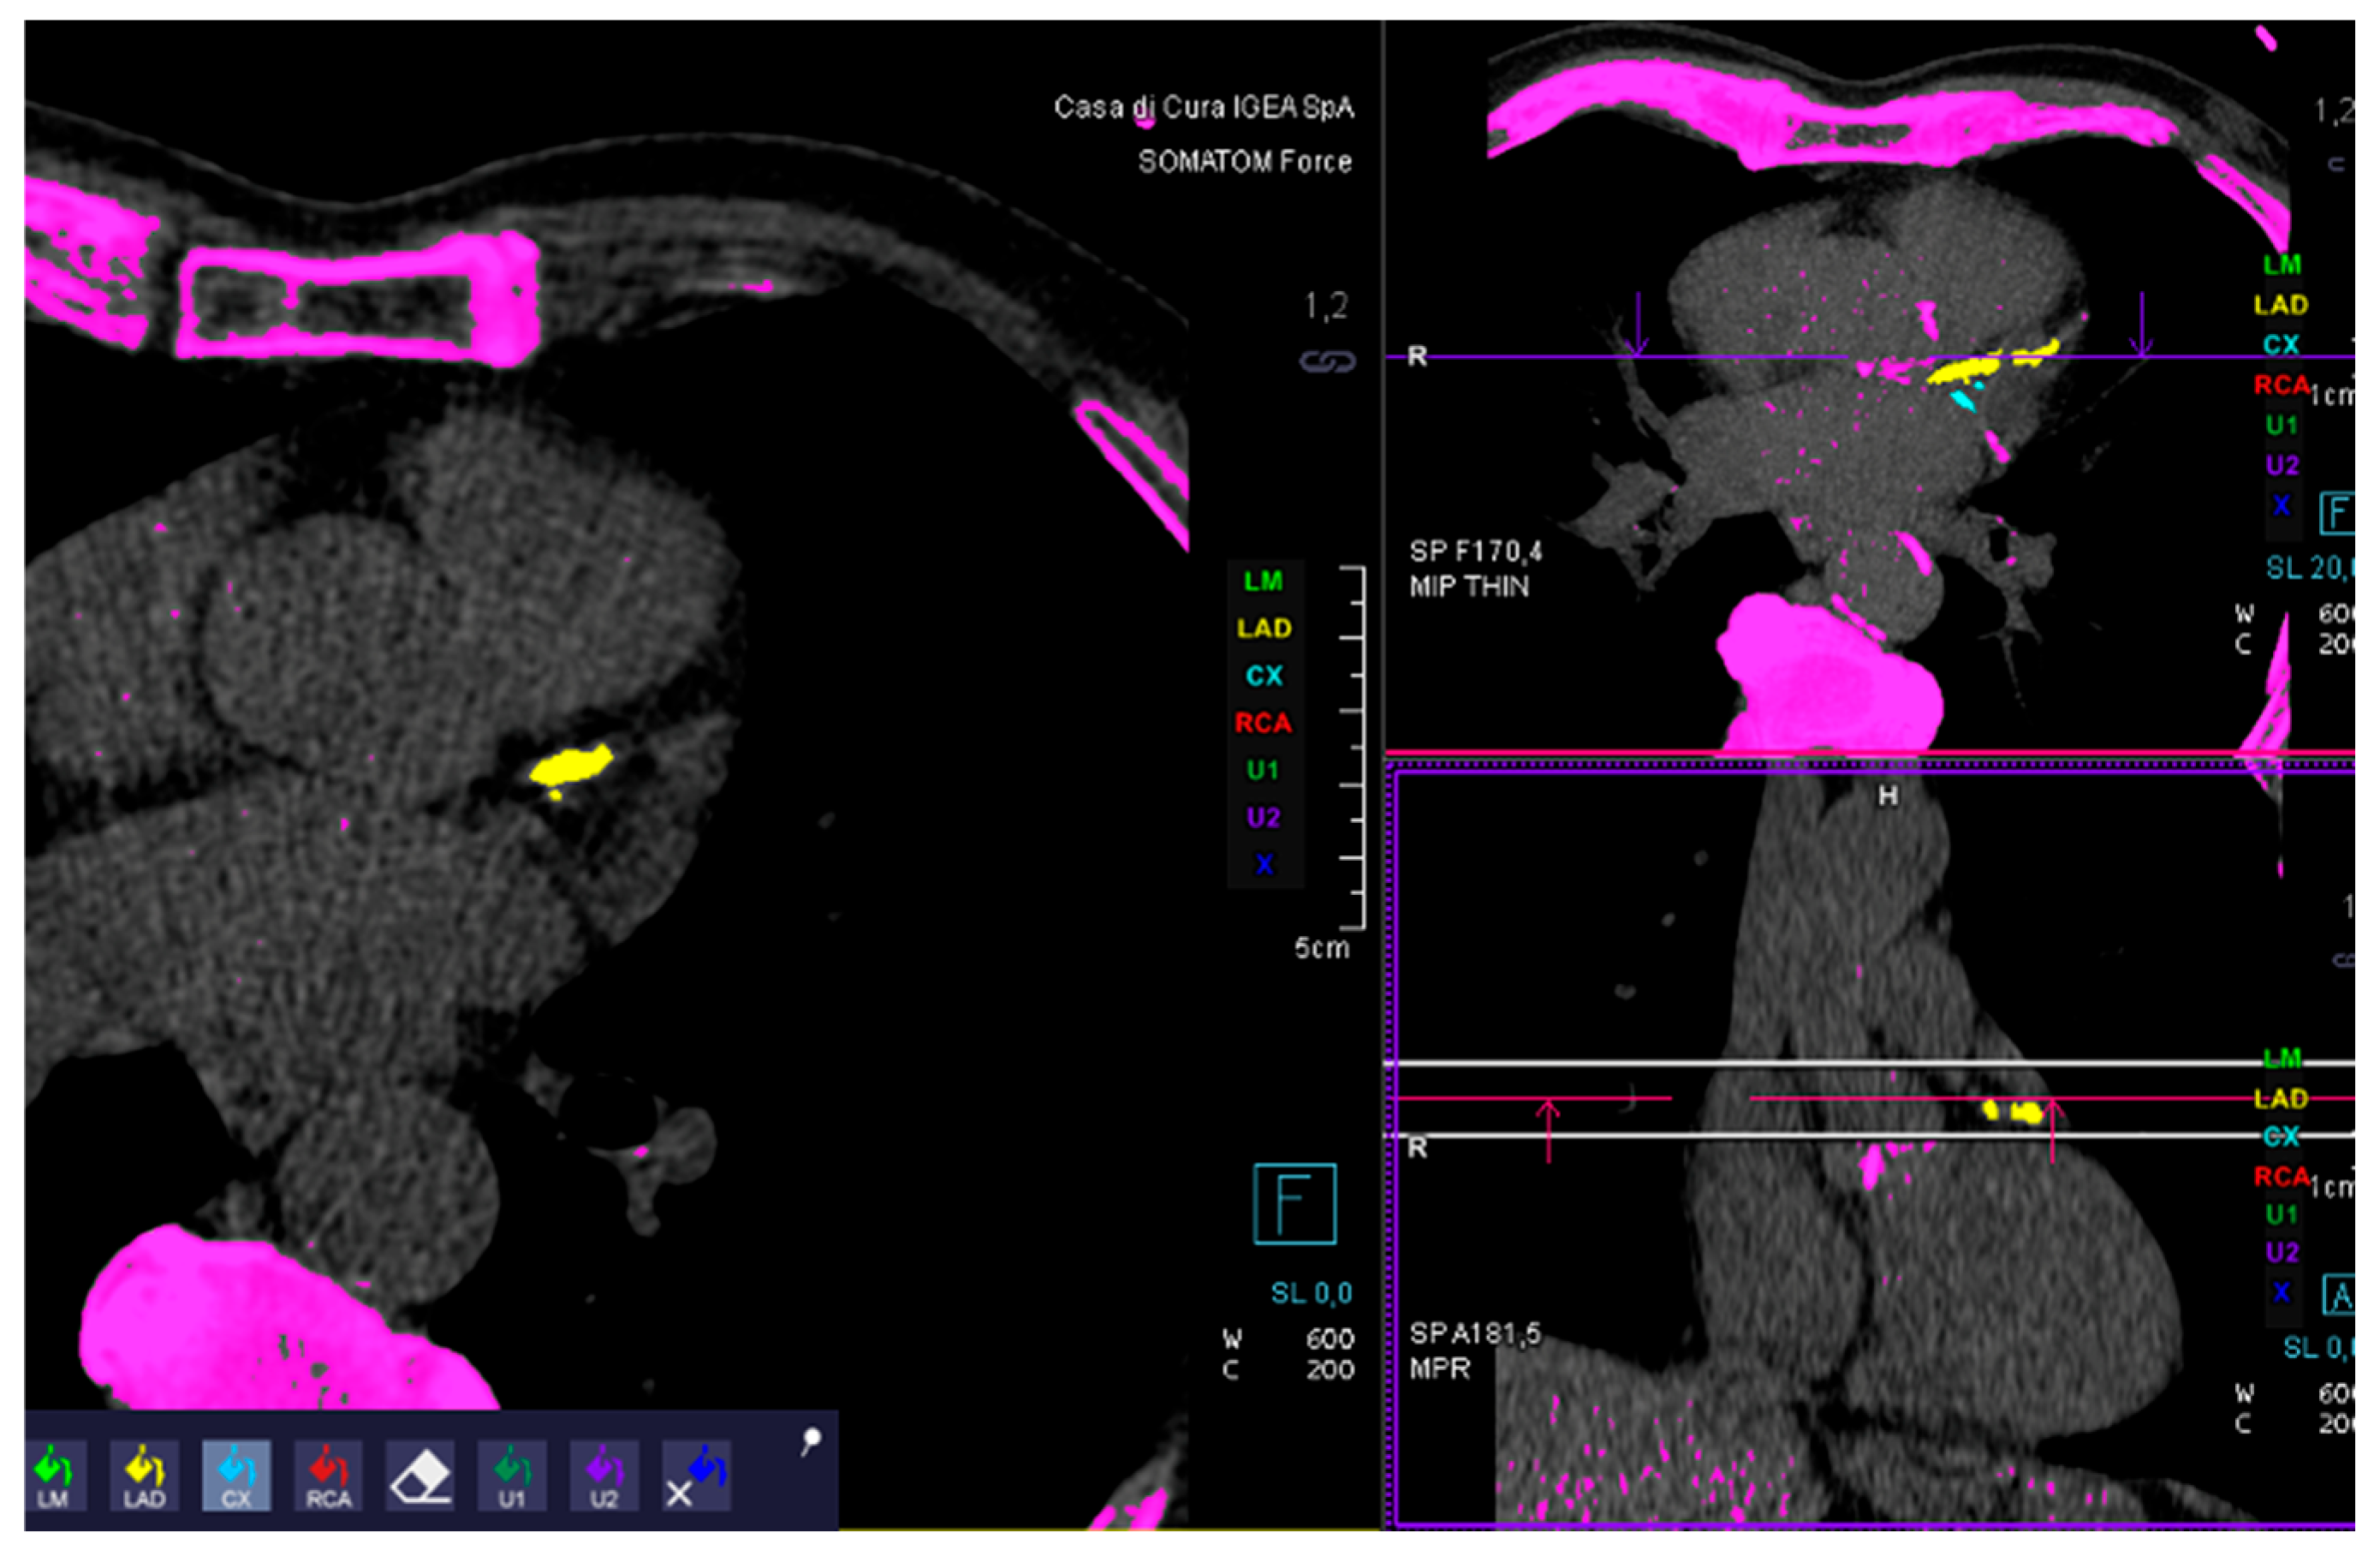

1.3. Images Analysis